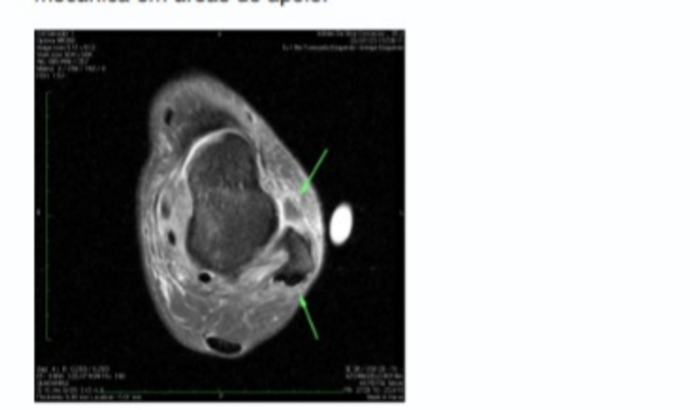

Logo abaixo está o laudo médico:Tenossinovite dos fibulares.Rotura completa do ligamento talofibular anterior, com edema e tecido cicatricial em suatopografia. Há pequeno corpo livre ossificado junto à topografia ligamentar Alterações pós-estiramento, com lesão parcial do ligamento calcaneofibular.Edema, com irregularidade das fibras ligamentares profundas do deltoide, indicando lesãoparcial.Focos de edema ósseo pós-contusional no maleolo medial e redordo medial do tálus, semtraços de fratura evidentes.Pequeno derrame articular tibiotalar e subtalar posterior, com focos de espessamentosinovial.Bursite intermetatársica do I e III espaços.Edema da tela subcutânea nas regiões perimaleolares.Obliteração do coxim adiposo plantar subjacente à cabeça do I metatarsiano, de natureza mecânica em áreas de apoio.